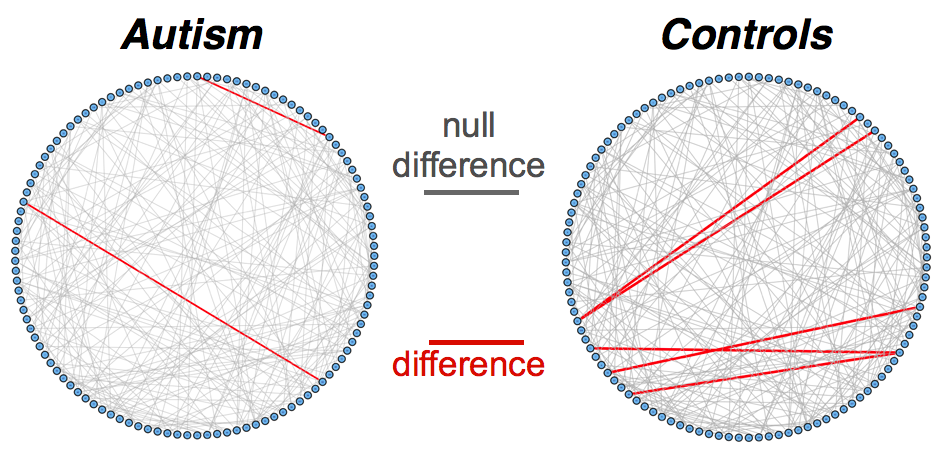

To understand the performance of this standard method, we present a small preview of our simulation study discussed later in Section 4. Briefly, we assume that each subject graph in group follows a small-world structure on nodes; in group , there are in addition 150 differential edges, meaning that and for all differential edges, . We generate data according to this model with time points and subjects in each group. Figure 1 illustrates the results of this standard approach as well as our new procedure, , which we will introduce later in Section 3. Part (a) gives ROC curves for the number of false positives verses true positives as each sequential test is rejected; parts (b) and (c) give the adjacency confusion matrix illustrating where the true and false positive as well as false negative edges are detected in the graph structure.

Our motivating simulation shows that the standard approach performs terribly in terms of both error control and statistical power. While the magnitude of the poor performance of this approach may seem astonishing, the poor performance should come as no surprise: The inferential procedure (e.g. test statistics) of the standard approach assume a one-level model that would be appropriate when the subject graphs are fixed and known or directly observed quantities. When these subject networks are unobserved, however, and must be estimated from finite data, these one-level test statistics are incorrect for our two-level problem. Specifically for two-level problems, the variance of parameters estimated by incorrectly assuming a one-level models is underestimated. For our problem, the extra source of variability arises from the graph selection procedure; we discuss challenges associated with this subsequently in Section 2.2. Incorrect variance estimates, however, are not the only problem with the standard approach: A more subtle problem arises from the fact that the proclivities of graph selection procedures for the Gaussian graphical model lead to biased estimates of the edge proportions, . As discussed in Section 2.3 and seen in Fig 1, graph selection false positives and false negatives do not occur at random throughout the network structure, leading to biased group level estimates.

2.2 Challenge I: Two Levels of Network Variability

For our two-level problem (1.1.1), we must account for two sources of network variability when conducting population inference: (i) variability between subjects within a group and (ii) variability of the network selection procedure within a single subject. To see this, let us study a real multi-subject fMRI example. In Figure 2, we show estimated functional brain networks for subjects from the UCLA fMRI ABIDE data set INDI (2013). We describe the details of this data set, our pre-processing, and brain parcellation later in the Case Study in Section 5. In the top and middle panels, we estimate brain networks for each subject using graph selection methods for Gaussian graphical models (see Section 3.1 for details) and plot these as circle graphs to easily visualize network differences. It is clear that there are not only differences between autistic subjects and control subjects, but there is also large heterogeneity across subjects within each group. This is well-known in the neuroimaging literature (Milham et al., 2012; Nielsen et al., 2013), and makes finding statistically significant differences between subject groups much more challenging.

Less well studied in neuroimaging, is the second source of variability which arises from estimating networks for each subject instead of directly observing the networks. In the bottom panel of Figure 2, we re-estimate brain networks for a single control subject with bootstrap resampled data. It is clear that there is major intra-subject variability arising from our graph selection procedure. Indeed in neuroimaging, test–re-test studies which conduct brain imaging on the same subject in repeated sessions have shown high variability in the subject’s estimated brain networks (Wang et al., 2011). This also motivates the necessity of using a two-level model like (1.1.1) for population network inference as opposed to the one-level model and test statistics of the standard procedure.